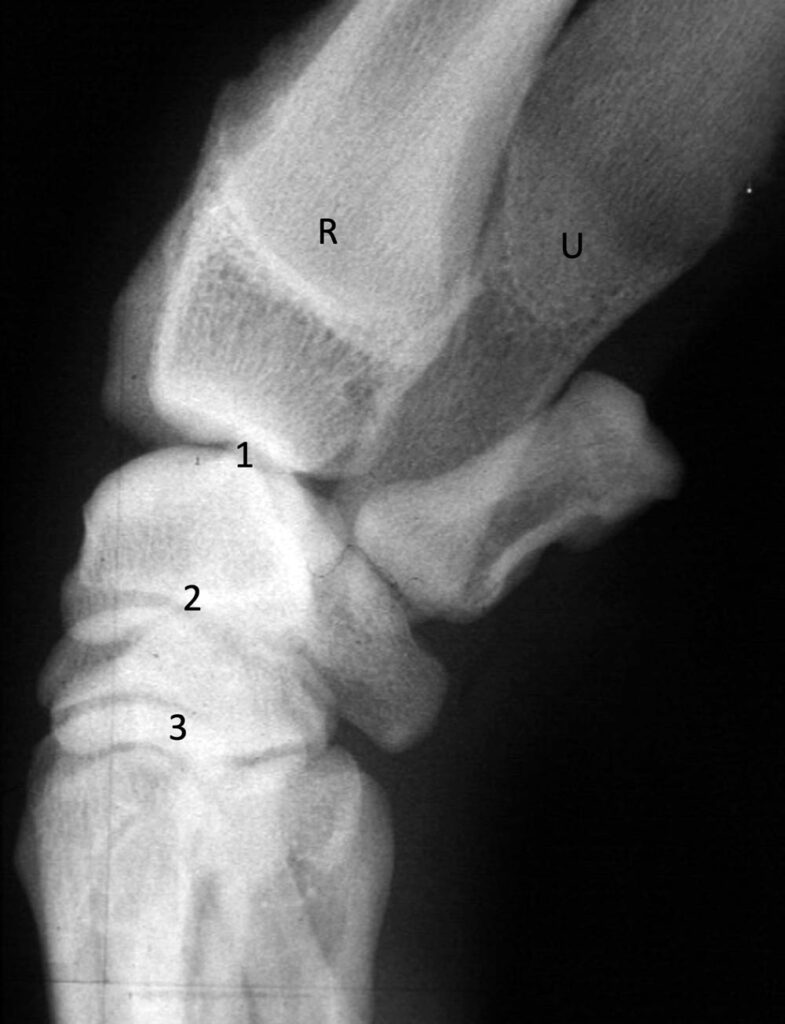

The carpal joint is a complex, three-level hinge joint. The three levels are the antebrachiocarpal joint, the intercarpal joint, and the carpometacarpal joint. Most of the movement in the carpus occurs at the antebrachiocarpal joint with the other two joints being low motion joints.